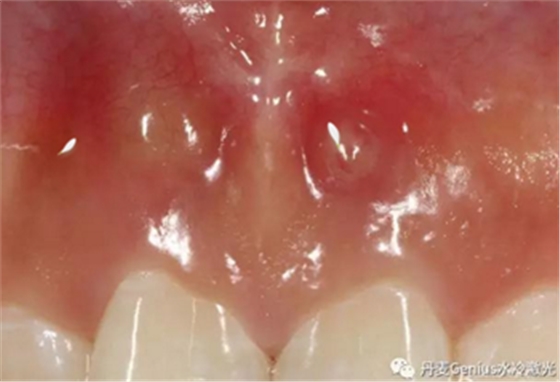

淺表黏膜膿腫切開引流

在常規(guī)消毒后,涂抹本品,再行切割。在更換藥物時,也可以涂抹

口腔潰瘍,燙傷,黏膜病

進(jìn)食前涂布,以防疼痛